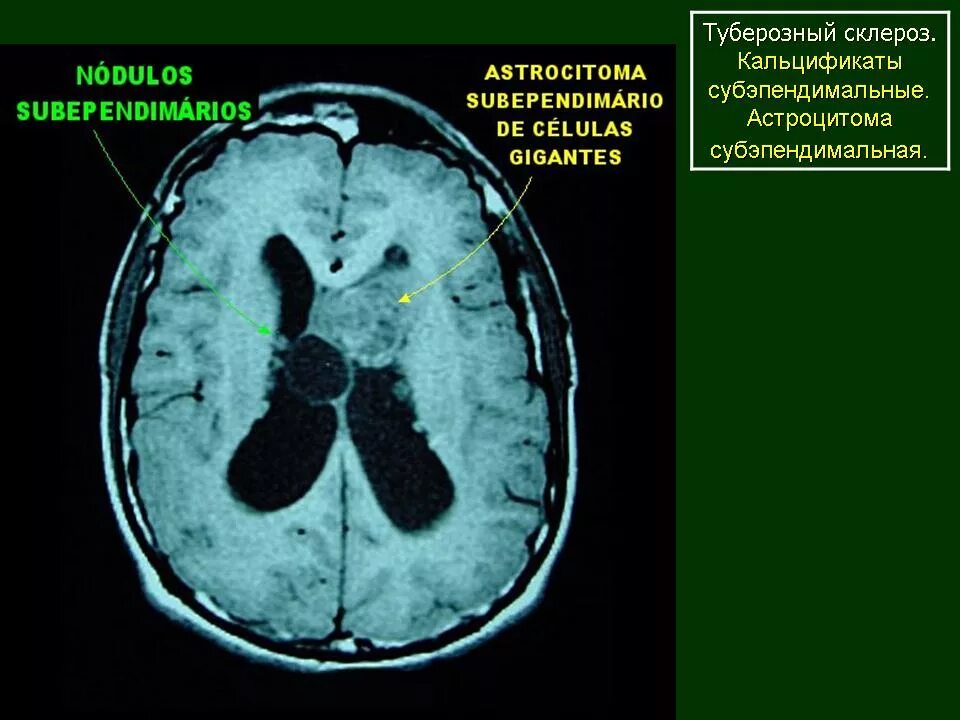

Туберкулезный склероз